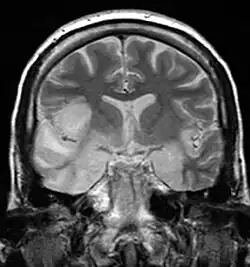

Kernspintomographie. Herpes-simplex-Enzephalitis (HSV-1) im temporo-basalen Bereich rechts (MRT mit T2-Gewichtung)

In der Magnetresonanztomographie, die für die Diagnose meist richtungsweisend ist, sind temporal und basal enzephalitische Herde mit dem Einsetzen zentralnervöser Symptome erkennbar. Die Computertomographie des Schädels weist in den ersten Tagen der Symptomatik regelhaft noch keine Auffälligkeiten auf. Auch Ableitungen im EEG zeigen erst nach fünf bis elf Tagen pathologische Allgemeinveränderungen im Sinne einer Enzephalitis, typischerweise mit epileptiformen Mustern über den frontalen und temporalen Regionen.